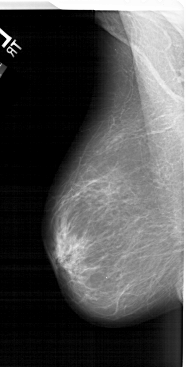

A_1299_1.RIGHT_MLO

RIGHT_MLO LINES 6166 PIXELS_PER_LINE 3541 BITS_PER_PIXEL 12 RESOLUTION 43.5 OVERLAY